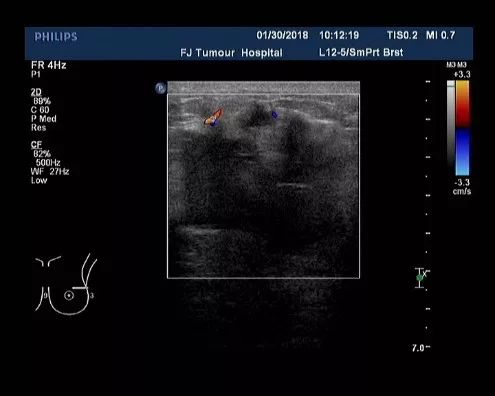

▎疗效评估: B超(2018-04):左乳外上象限探及一低回声区,大小约4.9cm×3.9cm,边缘不规则,可见成角、毛刺,内部回声不均;左腋中下组探及数个低回声,大者约2.5cm×1.6cm,边界尚清,类圆形,皮髓质分界不清,皮质不规则增厚,淋巴结门消失;右乳及右腋窝未见异常。